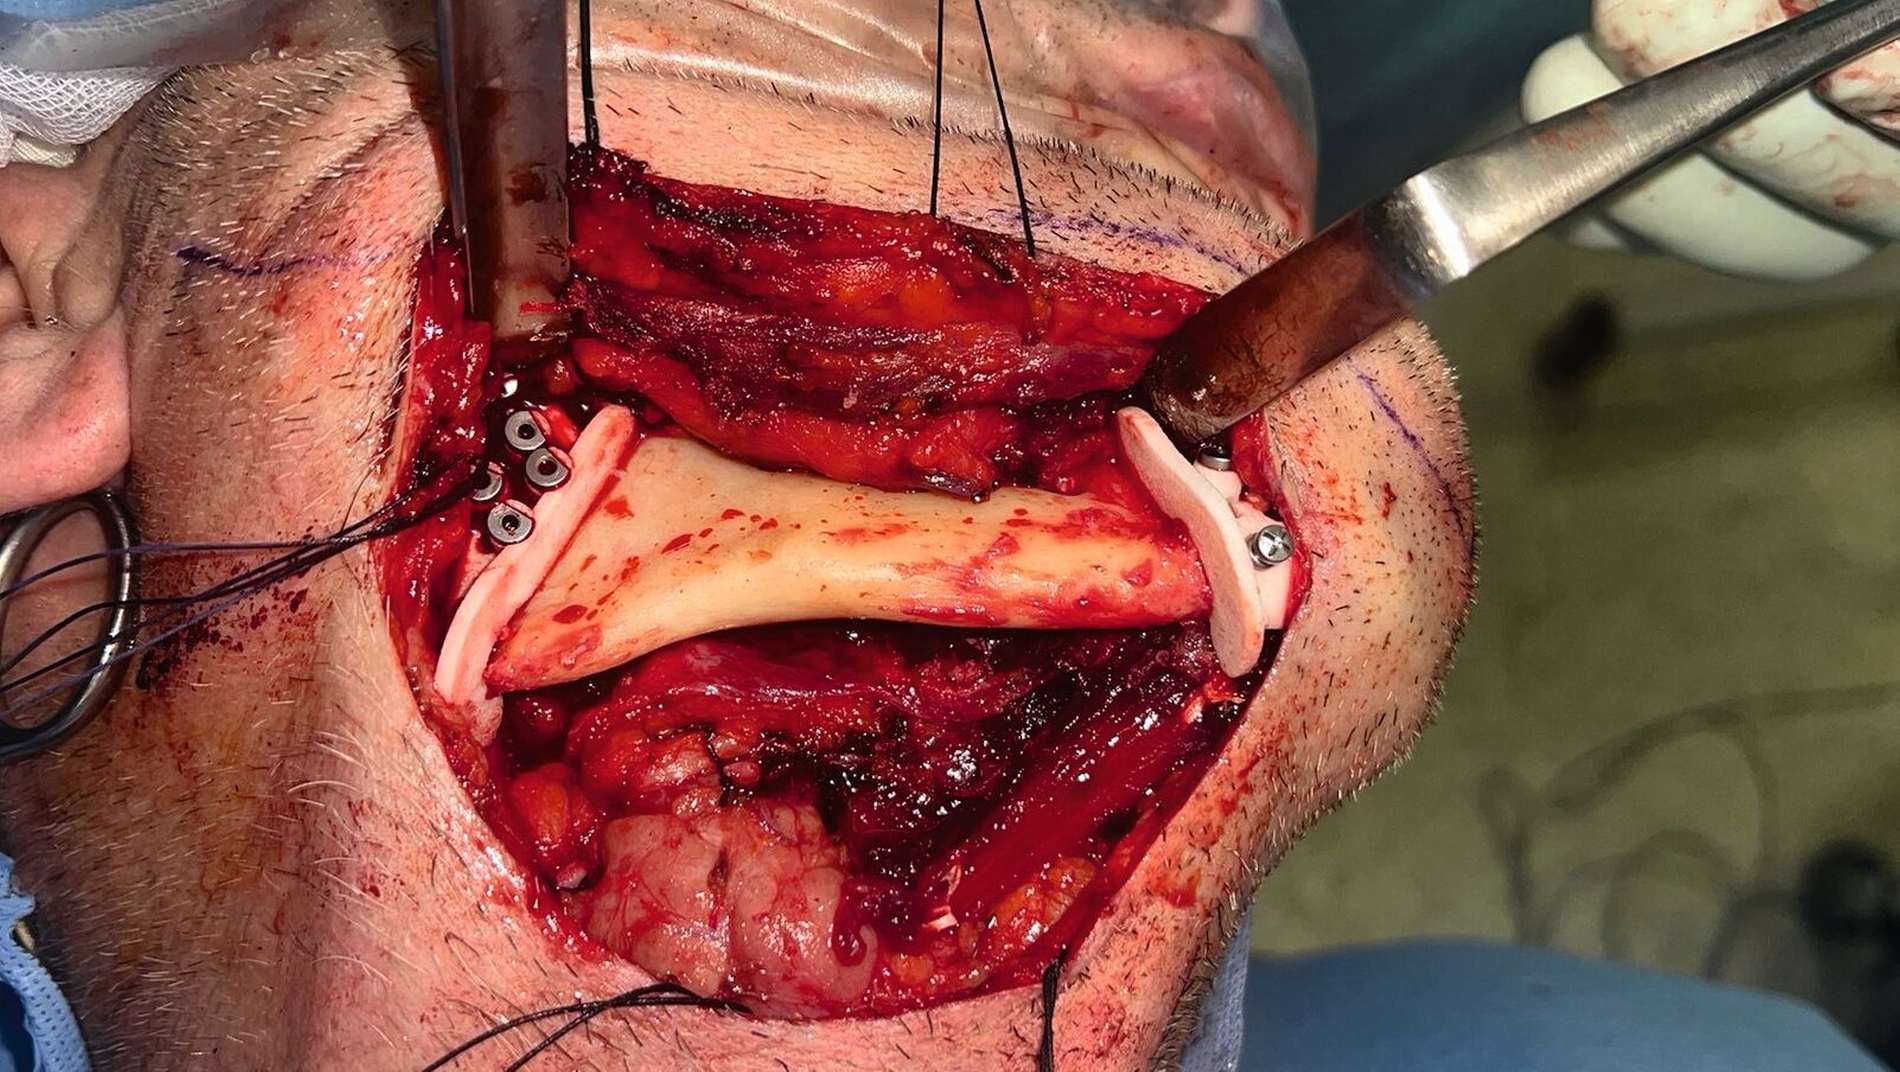

In Intubationsnarkose wurde die Kontinuitätsresektion von extraoral mittels CAD/CAM-gefertigten Schnittschablonen durchgeführt (Abbildung 5). Das entnommene Fibulatransplantat (Abbildung 6) wurde osteotomiert und mittels individuellen Osteosyntheseplatten zur Überbrückung des Defekts fixiert (Abbildung 7). Die notwendigen Gefäßanastomosen erfolgten End-zu-End an der Arteria thyroidea superior und End-zu-Seit an der Vena jugularis interna.